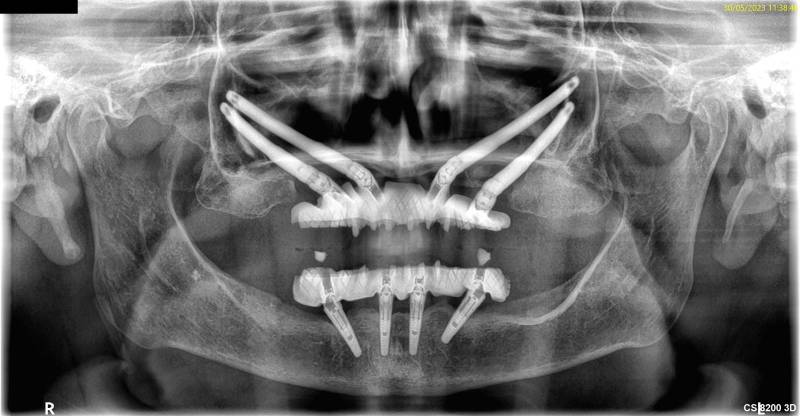

L'implant zygomatique, également connu sous le nom d'implant malaire, est une option de traitement utilisée au cabinet Implantys près de Mâcon pour ancrer des prothèses dentaires chez les patients qui ont une perte osseuse sévère dans la région maxillaire supérieure et qui ne peuvent pas bénéficier d'implants conventionnels en raison du manque de densité osseuse. L'implant zygomatique diffère donc des implants dentaires conventionnels qui sont, eux, insérés dans l'os maxillaire. Cet implant est conçu pour être fixé dans l'os zygomatique, également appelé os malaire, situé près de la pommette. Cette alternative vous est proposée par nos chirurgiens dentistes spécialisés en implantologie, au cabinet Implantys proche de Belleville-en-Beaujolais.

Le processus d'implantation zygomatique est plus complexe que celui des implants conventionnels. Il nécessite une évaluation et une planification approfondies, ainsi qu'une intervention chirurgicale réalisée par un spécialiste qualifié, comme vous en trouverez dans notre au cabinet Implantys près de Belleville-en-Beaujolais. Pendant la chirurgie réalisée sous anesthésie générale, l'implant zygomatique est fixé à l'os zygomatique de manière à fournir une base solide pour les prothèses dentaires, telles que les bridges ou les prothèses complètes.

Les photos illustrant nos cas cliniques avant/après présentent des personnes consentantes et les mêmes patients y figurent, respectivement, pour le résultat avant/après. Ces photos nont pas été retouchées. Nous attirons expressément votre attention sur le fait que le résultat observé est propre à la personne concernée et quun résultat identique ne peut être attendu pour une autre personne, en raison de la propre individualité de chacun.